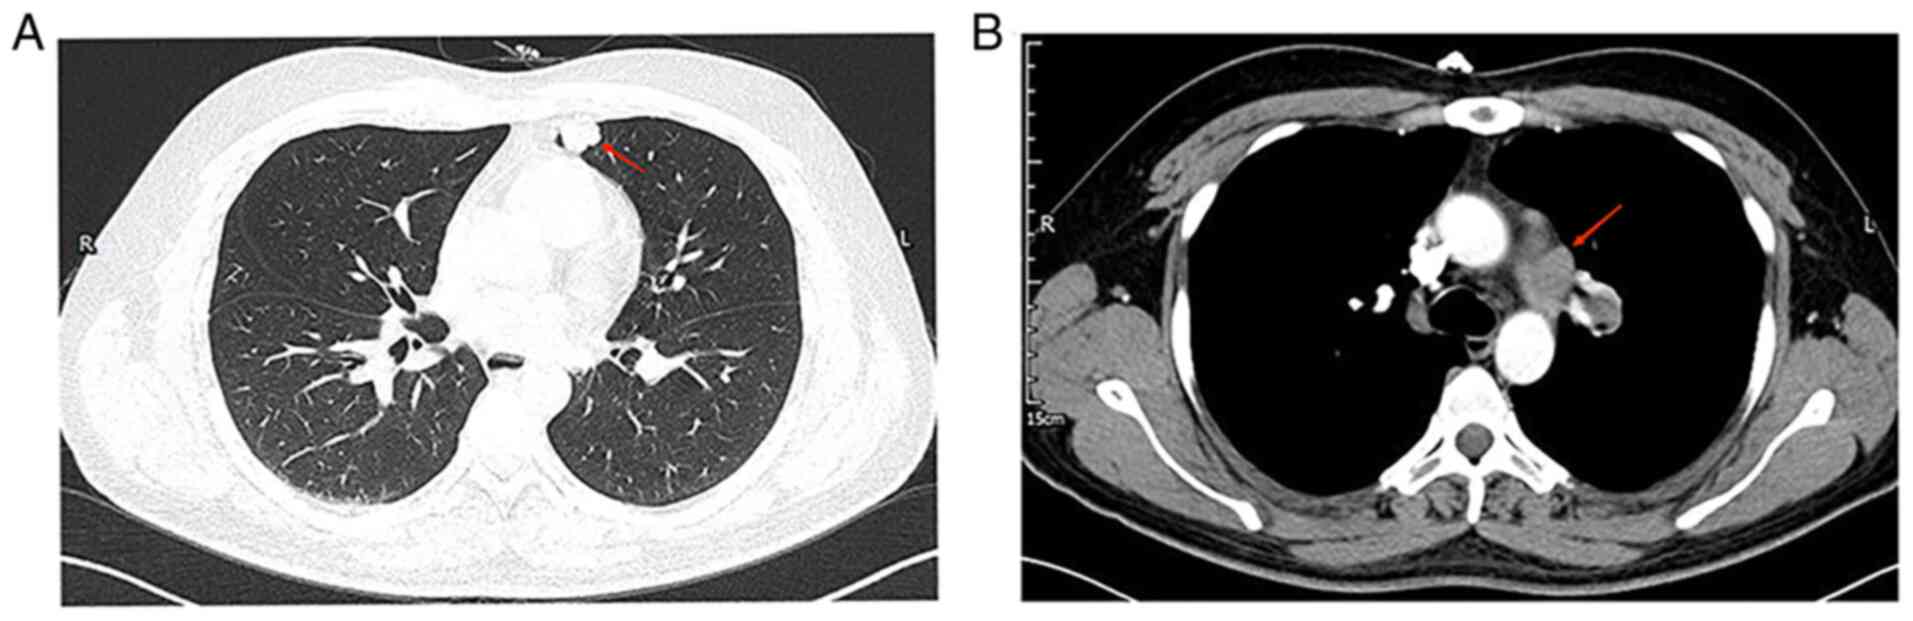

A 29-year-old male patient with no history of smoking presented at The Affiliated Hospital of Panzhihua University (Panzhihua, China) in March 2021 with a cough and chest pain. An enhanced chest CT scan revealed a nodular shadow in the left upper lung (~13×21 mm), a mass-like hyper-density shadow in the left upper lung hilum and enlarged lymph nodes in the left hilum and mediastinum (Fig. 1); no distant organ metastases were observed during the systemic examination. After five days, the patient underwent left upper lung lobectomy, left upper lobe pulmonary artery sleeve resection and systemic lymph node dissection. Post-operatively, the pathological report identified two tumor nodules, one small and one large, in the upper lobe of the left lung. The small nodule was close to the lung pleura (measuring ~2.5×2.0×1.1 cm) and diagnosed as lung adenocarcinoma by immunohistochemistry (IHC) (Fig. 2). The large nodule was located in the bronchus (measuring ~3.5×3.3×2.3 cm) and IHC supported pulmonary sarcomatoid carcinoma that was positive for pancytokeratin (partially) and vimentin (Fig. 3). The IHC protocols are provided in the supplemental data. These findings led to the diagnosis of adenocarcinoma of the upper lobe of the left lung combined with sarcomatoid carcinoma (T4N2M0 stage IIIB).